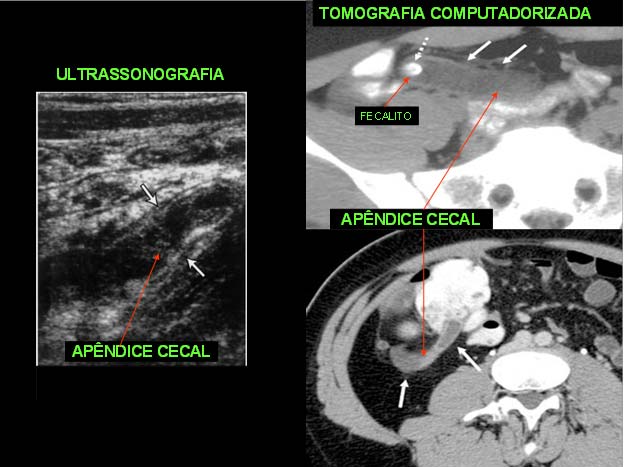

Além do minucioso exame clínico e laboratorial, com leucometria global e específica, a ultrassonografia (US) tem aumentado em muito o acerto diagnóstico nos casos atípicos. Este acerto varia de serviço para serviço e está ao redor de 85% - 90% . A tomografia poderá ser realizada em casos selecionados.